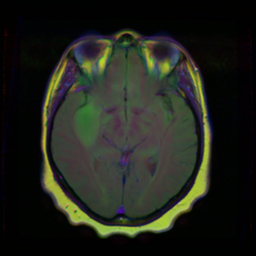

This notebook is used in conjunction with the Wallaroo Inference Server Free Edition for U-Net for Brain Segmentation. This provides a free Wallaroo license for performing inferences through the U-Net for Brain Segmentation model. The U-Net model is trained to detect lower-grade gliomas.

The Wallaroo Inference Server accepts pandas DataFrame or Apache Arrow tables as inference inputs. The sample file ./data/TCGA_CS_4944.png is used as the sample input.